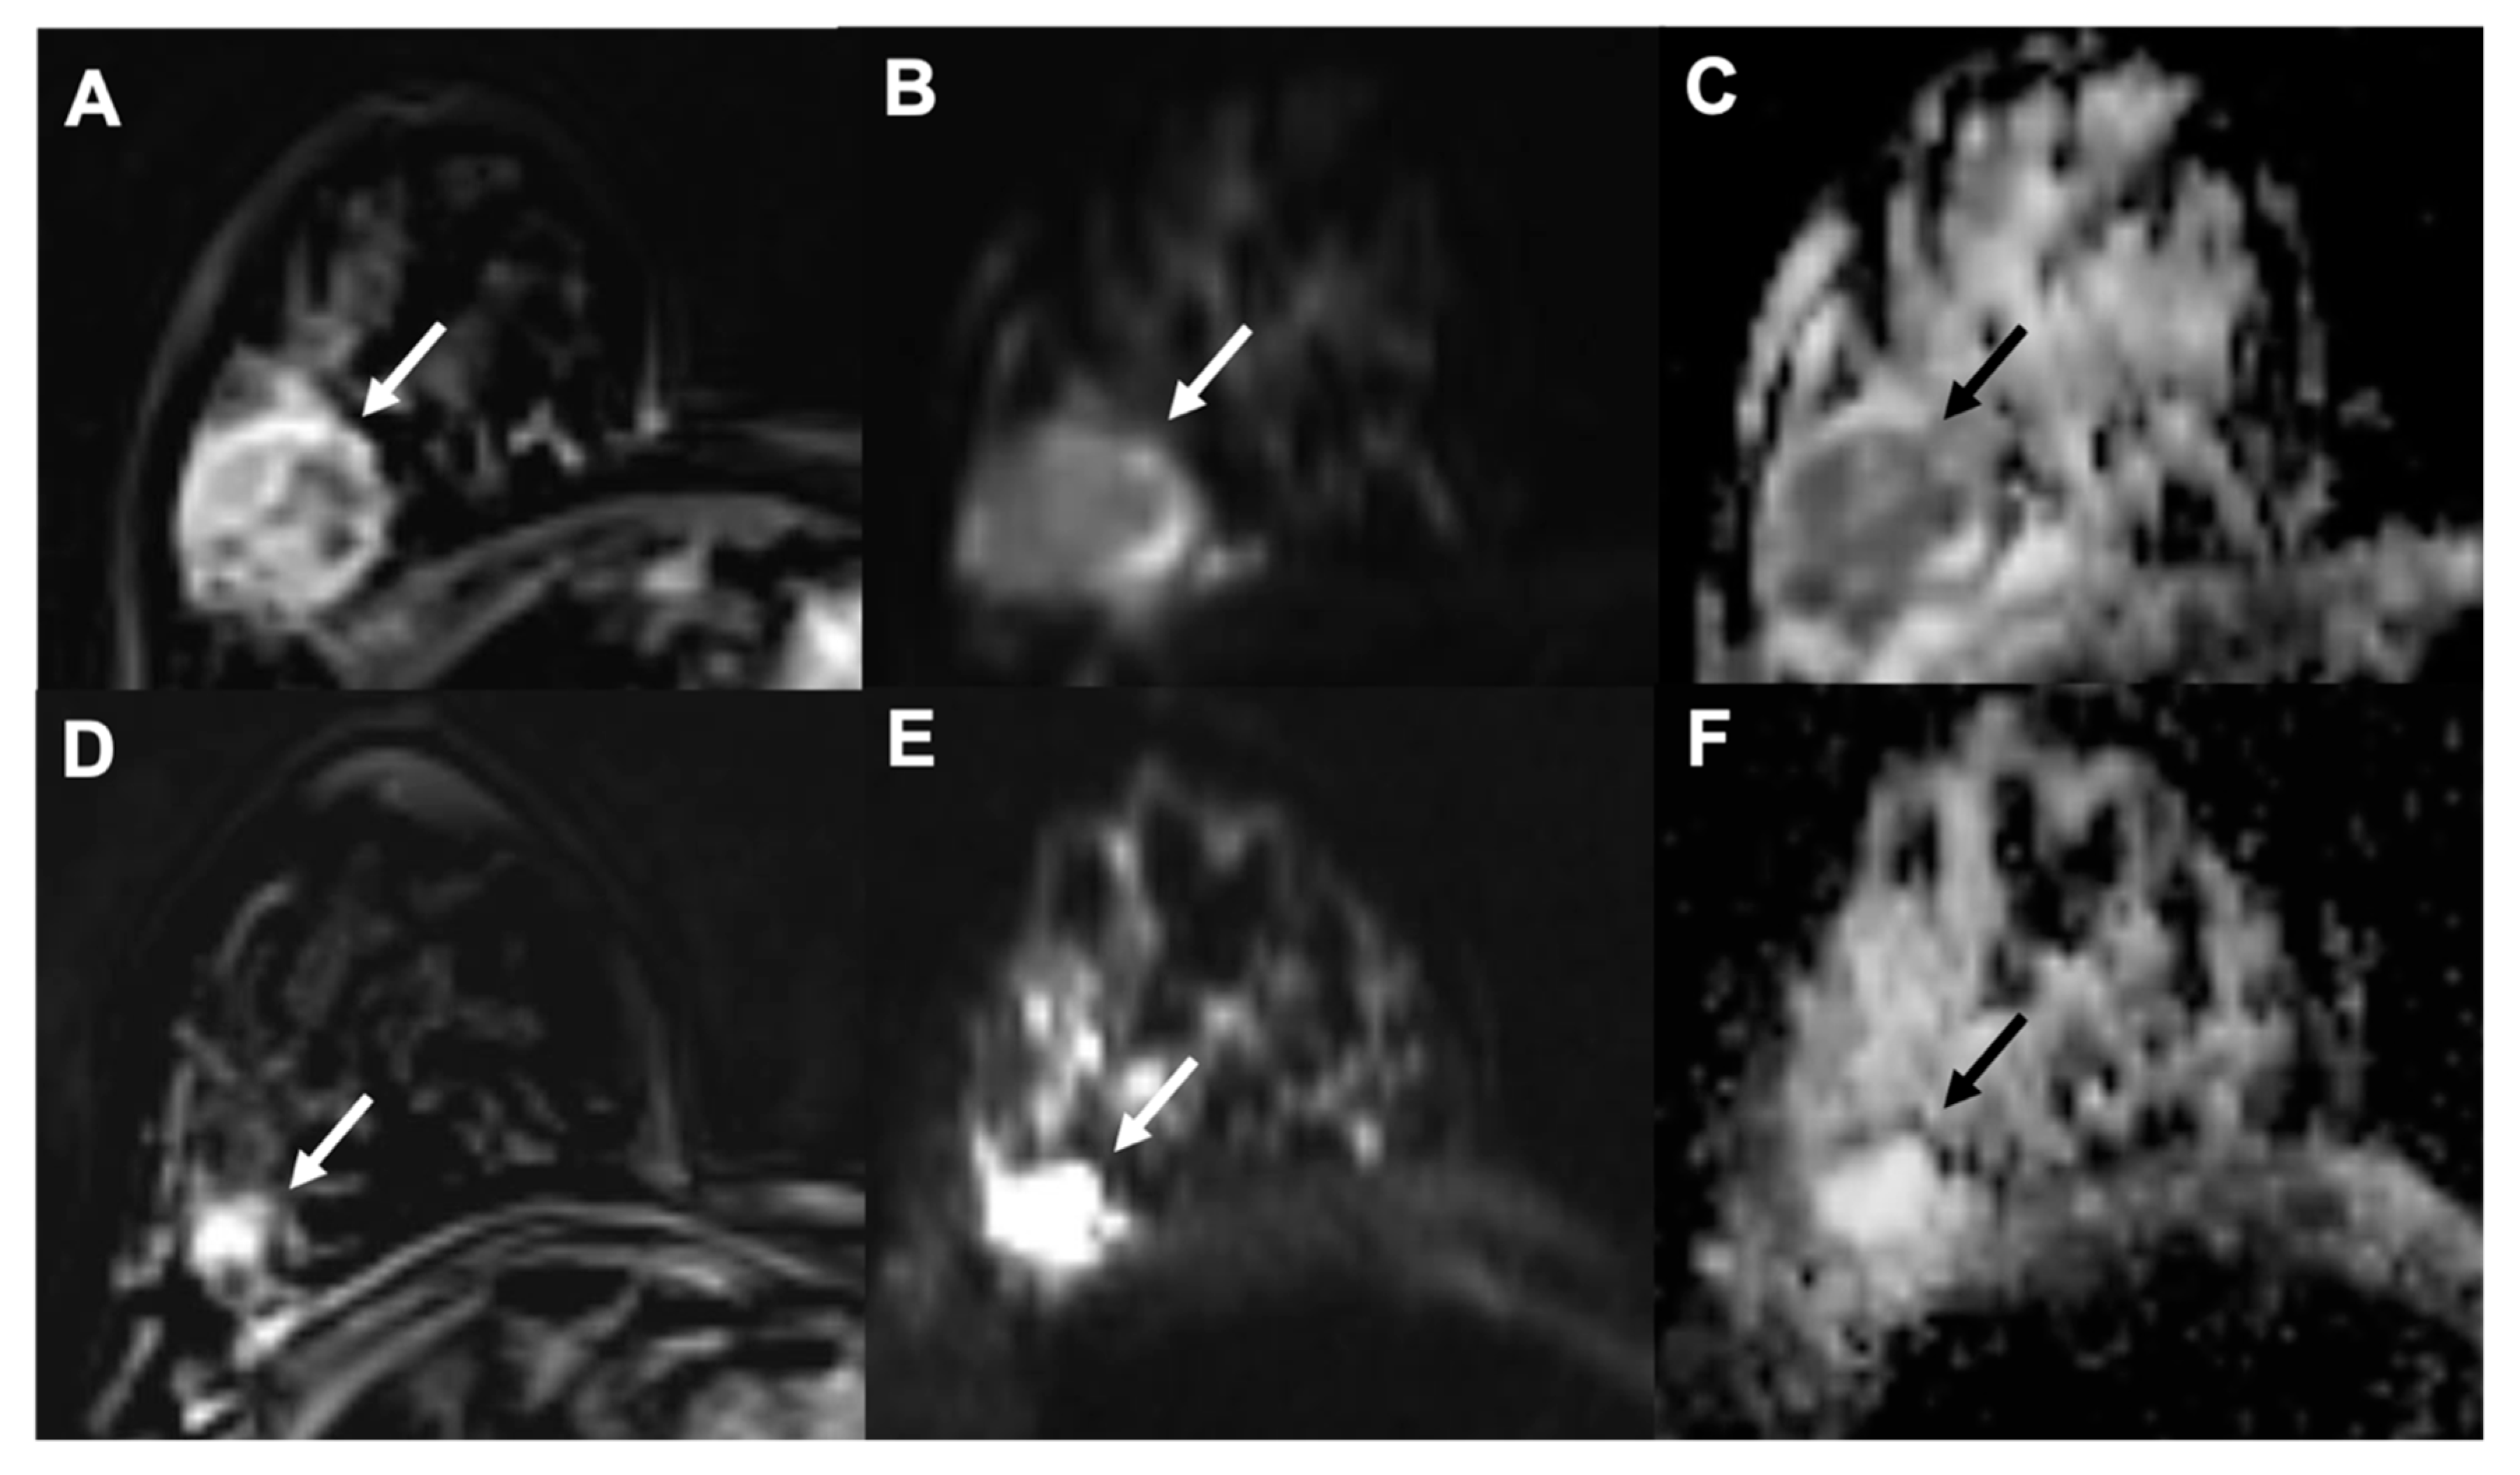

- Wu, L.; Hu, J.; Gu, H.; Hua, J.; Chen, J.; Xu, J. Can diffusion-weighted MR imaging and contrast-enhanced MR imaging precisely evaluate and predict pathological response to neoadjuvant chemotherapy in patients with breast cancer? Breast Cancer Res. Treat. 2012, 135, 17–28. [Google Scholar] [CrossRef]

- Hahn, S.Y.; Ko, E.Y.; Han, B.-K.; Shin, J.H. Role of diffusion-weighted imaging as an adjunct to contrast-enhanced breast MRI in evaluating residual breast cancer following neoadjuvant chemotherapy. Eur. J. Radiol. 2014, 83, 283–288. [Google Scholar] [CrossRef] [PubMed]

- Sharma, U.; Danishad, K.K.A.; Seenu, V.; Jagannathan, N.R. Longitudinal study of the assessment by MRI and diffusion-weighted imaging of tumor response in patients with locally advanced breast cancer undergoing neoadjuvant chemotherapy. NMR Biomed. 2009, 22, 104–113. [Google Scholar] [CrossRef] [PubMed]